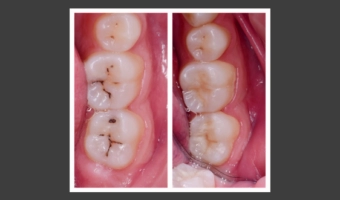

Фісурний карієс відноситься до поширених стоматологічних проблем, особливо у дітей і підлітків, хоча нерідко діагностується й у дорослих. Початкова стадія нерідко протікає без симптомів, а поглиблене руйнування дентину окрім пломбування потребуватиме складнішого відновлення. ...